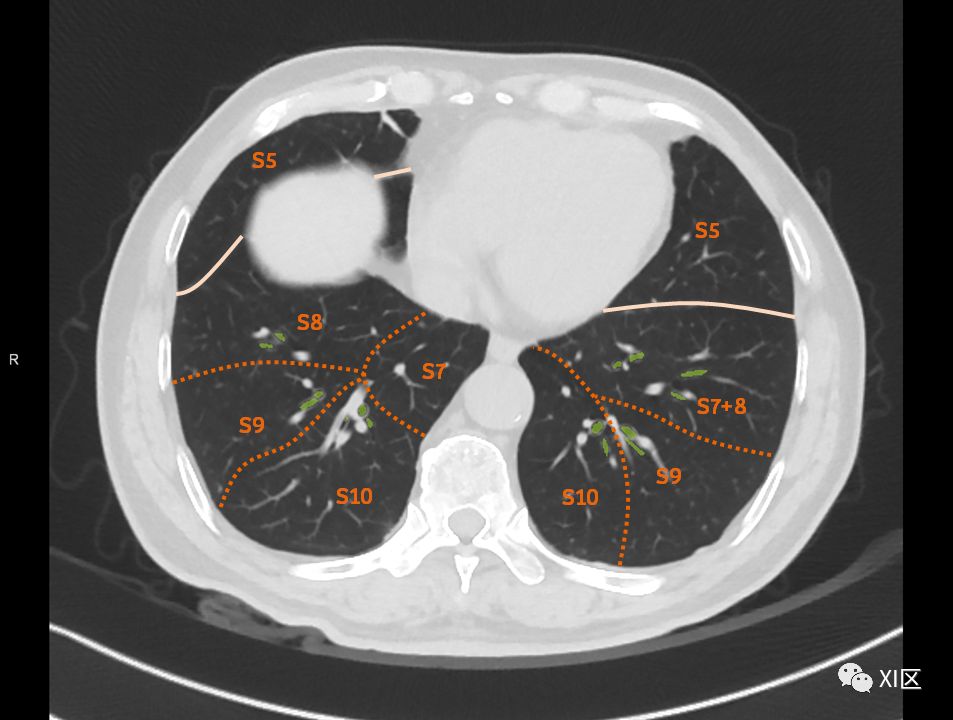

肺的断层分段示意图

在进行肺的分段时,可以上下观察浏览,沿着相应气管的走形可以更容易准确地进行分段。